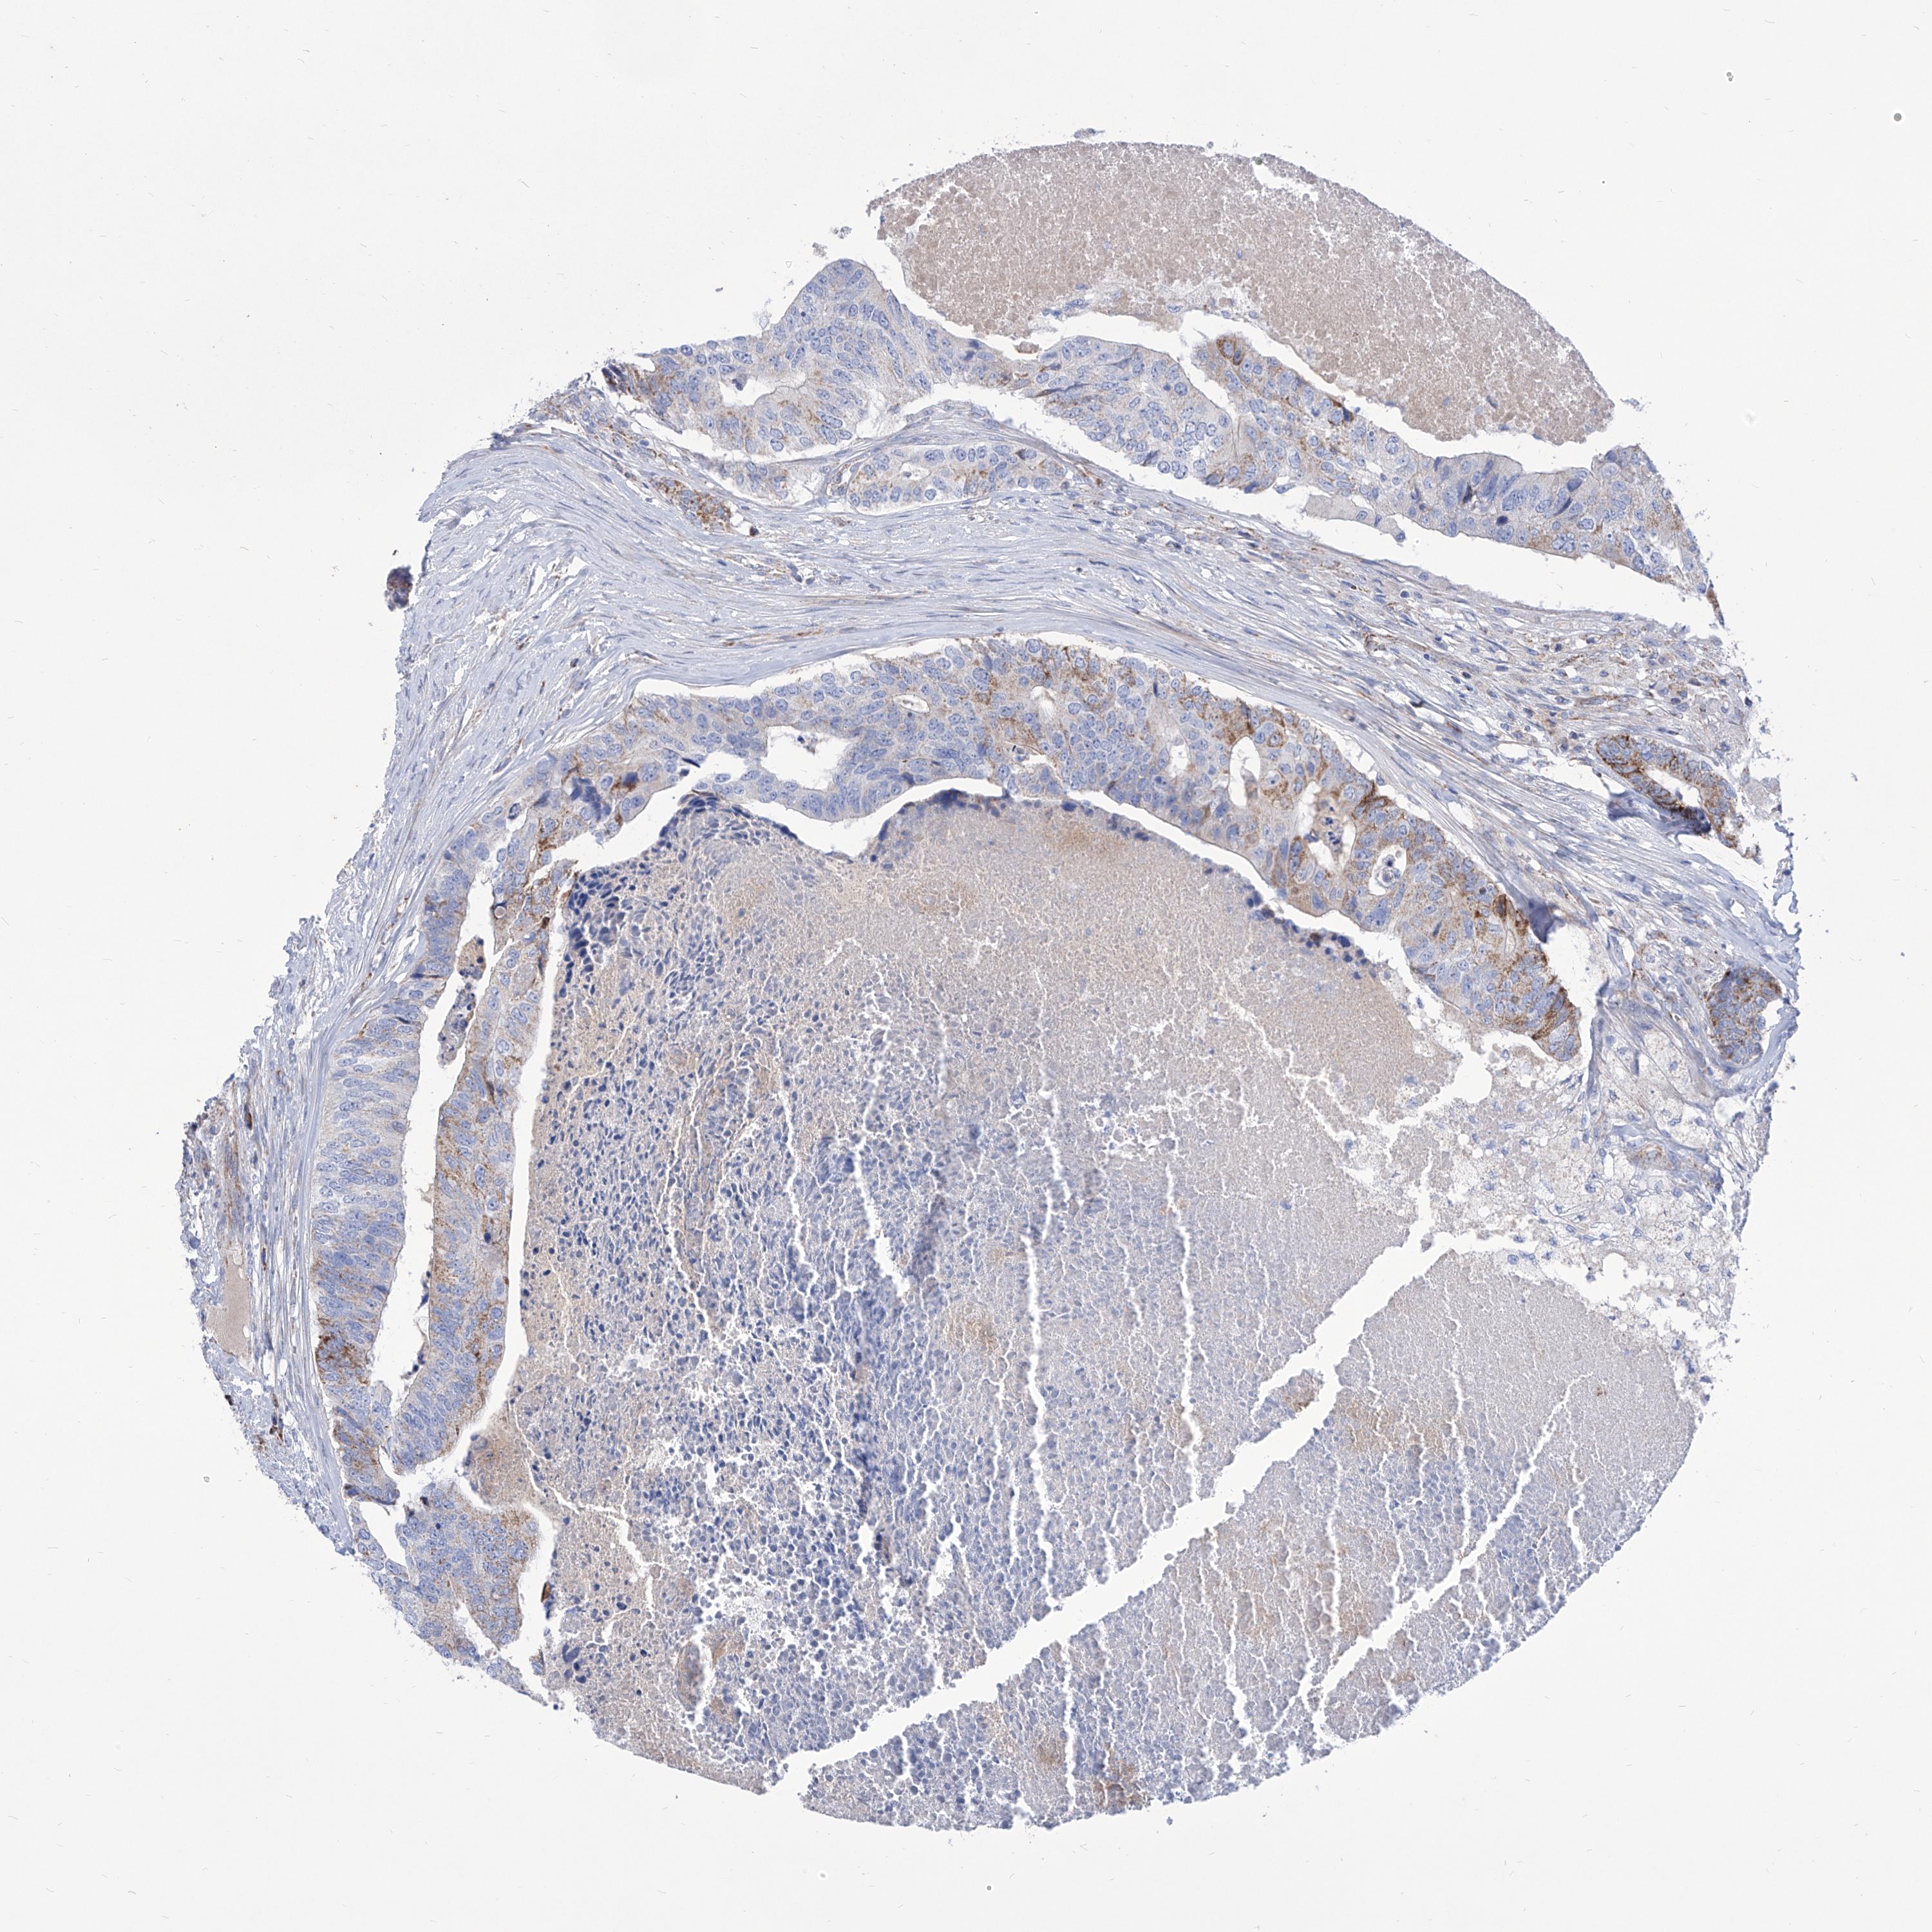

COLON ADENOCARCINOMA (VALIDATION) - Interactive survival scatter ploti

The Survival Scatter plot shows the clinical status (i.e. dead or alive) for all individuals in the patient cohort, based on the same data that underlies the corresponding Kaplan-Meier plots. Patients that are alive at last time for follow-up are shown in blue and patients who have died during the study are shown in red.

The x-axis shows the expression levels (FPKM) of the investigated gene in the tumor tissue at the time of diagnosis. The y-axis shows the follow-up time after diagnosis (years). Both axes are complimented with kernel density curves demonstrating the data density over the axes. The top density plot shows the expression levels (FPKM) distribution among dead (red) and alive patients (blue). The right density plot shows the data density of the survived years of dead patients with high and low expression levels respectively, stratified using the cutoff indicated by the vertical dashed line through the Survival Scatter plot. This cutoff is automatically defined based on the FPKM cutoff that minimizes the p-score. The cutoff can be changed by dragging the vertical line or by entering a cutoff value in the square labeled "Current cut-off".

Under the Survival Scatter plot the p-score landscape (black curve; left axis) is shown together with dead median separation (red curve; right axis). Dead median separation is the difference in median mRNA expression between patients who have died with high and low expression, respectively. It is calculated as follows: median FPKM expression of dead patients with high expression - median FPKM expression of dead patients with low expression. This is intended to aid the user in visually exploring custom cutoffs and the associated p-scores and dead median separation.

Individual patient data is displayed and can be filtered by clicking on one or more of the category buttons on the top of the page. Categories describing expression level and patient information include: high, low, alive, dead, female, male and tumor stages. The scale of the x-axis can be toggled between linear and log-scale by clicking on the "x log" button. Mouse-over function shows TCGA ID, patient information and mRNA expression (FPKM) for each patient.

& Survival analysisi

Kaplan-Meier plots summarize results from analysis of correlation between mRNA expression level and patient survival. Patients were divided based on level of expression into one of the two groups "low" (under cut off) or "high" (over cut off). X-axis shows time for survival (years) and y-axis shows the probability of survival, where 1.0 corresponds to 100 percent.

SRBD1 is not prognostic in Colon Adenocarcinoma (validation)

Best expression cut offi

Based on the FPKM value of each gene, patients were classified into two groups and association between prognosis (survival) and gene expression (FPKM) was examined. The best expression cut-off refers the FPKM value that yields maximal difference with regard to survival between the two groups at the lowest log-rank P-value. Best expression cut-off was selected based on survival analysis .

When clicking on this number, the vertical dashed line indicating cut-off, the interactive survival plot, and the Kaplan-Meier curve will be adjusted to show results based on the best expression cut-off.

: 16.22

Median expressioni

Median expression refers to the median FPKM value calculated based on the gene expression (FPKM) data from all patients in this dataset. When clicking on this number, the vertical dashed line indicating cut-off, the interactive survival plot, and the Kaplan-Meier curve will be adjusted to show results based on the median expression.

: N/A

P scorei

Log-rank P value for Kaplan-Meier plot showing results from analysis of correlation between mRNA expression level and patient survival.

N/A

5-year survival highi

5-year survival for patients with higher expression than the expression cutoff.

For melanoma and glioma, 3-year survival is shown.

5-year survival lowi

5-year survival for patients with lower expression than the expression cutoff.

TCGA RNA samplesi

RNA-seq data is reported as average FPKM (number Fragments Per Kilobase of exon per Million reads), generated by the The Cancer Genome Atlas (TCGA) .

Normal distribution across the dataset is visualized with box plots, shown as median and 25th and 75th percentiles. Points are displayed as outliers if they are above or below 1.5 times the interquartile range. FPKM values of the individual samples are presented next to the box plot.

Average pTPM 14.1

Number of samples 486